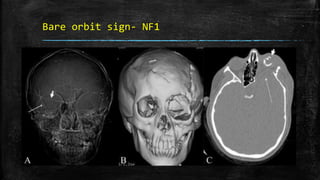

• #90 Bare orbit sign. Frontal CT scan scannogram of the head (A) shows a bare and large orbit on the left, with absence of the greater wing of the left sphenoid bone, in this patient with neurofibromatosis type 1. Note the normal lesser (thick small arrow) and greater (thin long arrow) wings of the sphenoid on the right side. Frontal surface-shaded display, 3D view of the skull (B) shows a large left orbit with dysplasia of the sphenoid wing. Axial CT scan image (C) shows anterior herniation of the left temporal lobe (thin long arrow) because of the dysplastic sphenoid bone. The left globe is small and calcified (phthisis bulbi) (thick short arrow) due to plexiform neurofibromatosis of the left orbit